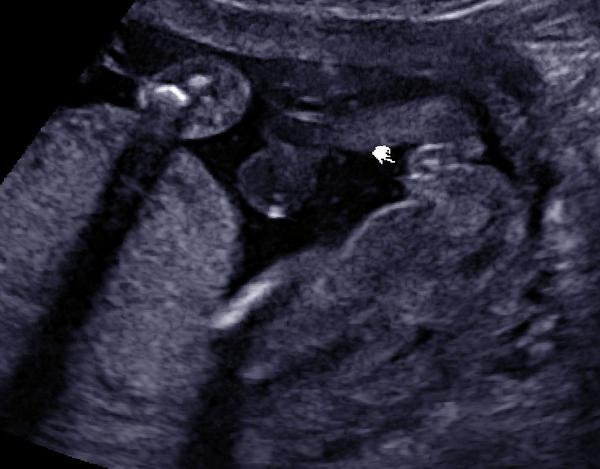

@zouzalka1982 tady posílám potvrzenou holčičku

@zouzalka1982 určitě dej vědět. Všichni říkali, že u holčiček je vidět kávový zrno. No, u té mojí mi to zrno ani při troše fantazie nepřipomíná. Ale holčička to nejspíš opravdu bude. Už mi ji od cca 16tt řekli 3 doktoři. Nikde nic netrci, tak to snad bude. Jistota samozřejmě bude až po porodu.

Já bych teda řekla, ze holčička, pipinku vidim🤔Každopádně držím palecky. Mám doma 2 kočky a utz byl hodně podobný tvému.